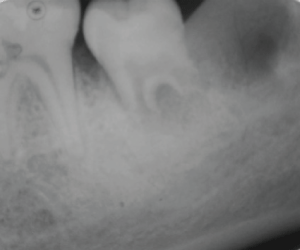

Fourteen days later, the transplanted tooth was in good condition. In the 34th day, continued root formation was observed (Figure 9 and Figure 10). After 4 months and 24 days, the transplanted tooth continued to be healthy as well as the gums around it. Also, the patient showed good oral hygiene. By using a radiographic exam, the continued root formation was seen (Figure 11).

Figures 11: Radiograph of the autotransplanted tooth 4 months and 24 days later.